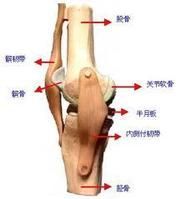

細菌侵入關節後,先有滑膜炎,關節滲液,關節有腫脹及疼痛。病情發展後,積液由漿液性轉為漿液纖維蛋白性,最後則為膿性。當關節受累後,病變逐漸侵入軟骨及骨質,最後發生關節僵硬。關節化膿後,可穿破關節囊及皮膚流出,形成竇道,或蔓延至鄰近骨質,引起化膿性骨髓炎。此外,由於關節囊的鬆弛及肌肉痙攣,亦可引起病理性脫臼,關節呈畸形,喪失功能。

細菌侵入關節後,先有滑膜炎,關節滲液,關節有腫脹及疼痛。病情發展後,積液由漿液性轉為漿液纖維蛋白性,最後則為膿性。當關節受累後,病變逐漸侵入軟骨及骨質,最後發生關節僵硬。關節化膿後,可穿破關節囊及皮膚流出,形成竇道,或蔓延至鄰近骨質,引起化膿性骨髓炎。此外,由於關節囊的鬆弛及肌肉痙攣,亦可引起病理性脫臼,關節呈畸形,喪失功能。根據細菌毒力、機體防禦能力及感染的時限,有下述三種不同時期的改變。

(一)漿液性滲出液:滑膜腫脹,充血、白細胞浸潤, 滲出液增多, 關節液呈清晰的漿液狀。如病人抵抗力強,細菌毒性小,並得到及時的治療、滲出液逐漸減少而獲痊癒,關節功能可恢復正常。治療不當,雖有時表現暫時性的好轉,而後再復發,或進一步惡化,形成漿液纖維蛋白性或膿性滲出液。

(二)漿液纖維蛋白性滲出液,滑膜炎程度加劇,滑膜不僅充血,且有更明顯的炎症,滑膜面上形成若干纖維蛋白,但關節軟骨面仍不受累。關節液呈絮狀。含有大量粒性白細胞及少量單核細胞,細菌培養多呈陽性。關節周圍亦有炎症。在此期雖能得以控制,但容易引起關節粘連,使關節功能有一定程度的損失。

(三)膿性滲出液: 是急性關節炎中最嚴重的類型和階段。感染很快就波及到整個關節及周圍組織,關節內有多量膿液。關節囊及滑膜腫脹,肥厚,白細胞浸潤,並有局部壞死。關節軟骨不久即被溶解,這是由於膿液內有死亡的白細胞所釋出的蛋白分解酶的作用,將關節軟骨面溶解所致。關節內積膿而壓力增加,可以破壞韌帶及關節囊引起穿孔,使關節周圍軟組織發生蜂窩織炎或形成膿腫,甚至穿破皮膚、形成竇道。治療困難,可經久不愈。即使癒合,關節常發生纖維性成骨性強直。